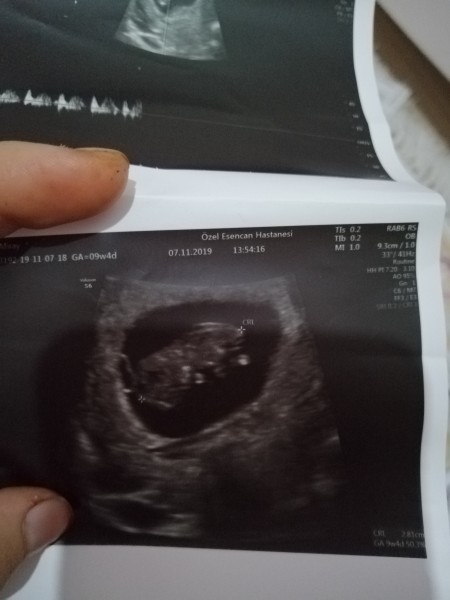

Cinsşyette tahmini

cinsiyet tahminiiii

Kesen yuvarlak canım başı da sağda sanki kız :)

Erkeğe benziyor ama daha erken değişebilir dedi 12 haftalıktık o zaman :))

Şuan 13+5teyiz :)